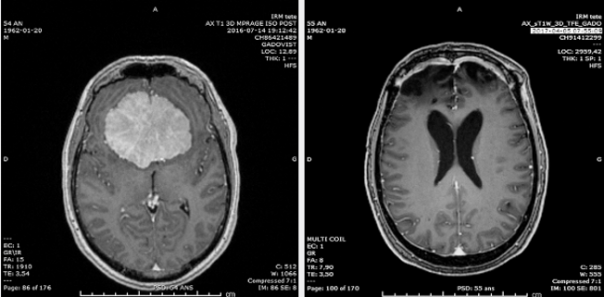

Финеас Кейдж и лобная доля

В 1848 году Кейдж, строитель железной дороги (вверху), выжил после взрыва, хотя сильно пострадал: левую лобную долю его мозга проткнуло железным прутом. Выздоровев, из дружелюбного и вежливого человека он превратился в черствого и безразличного.

А вот пример из современной жизни одного канадца: в лобной доле у него образовалась доброкачественная опухоль, и, когда ему ее удалили, его жена сказала хирургам: «Спасибо, что вернули мне мужа». Снимки МРТ (внизу) показывают, как выглядел его мозг до и после операции. Такие случаи помогают понять, как определенные участки мозга управляют нашим поведением.